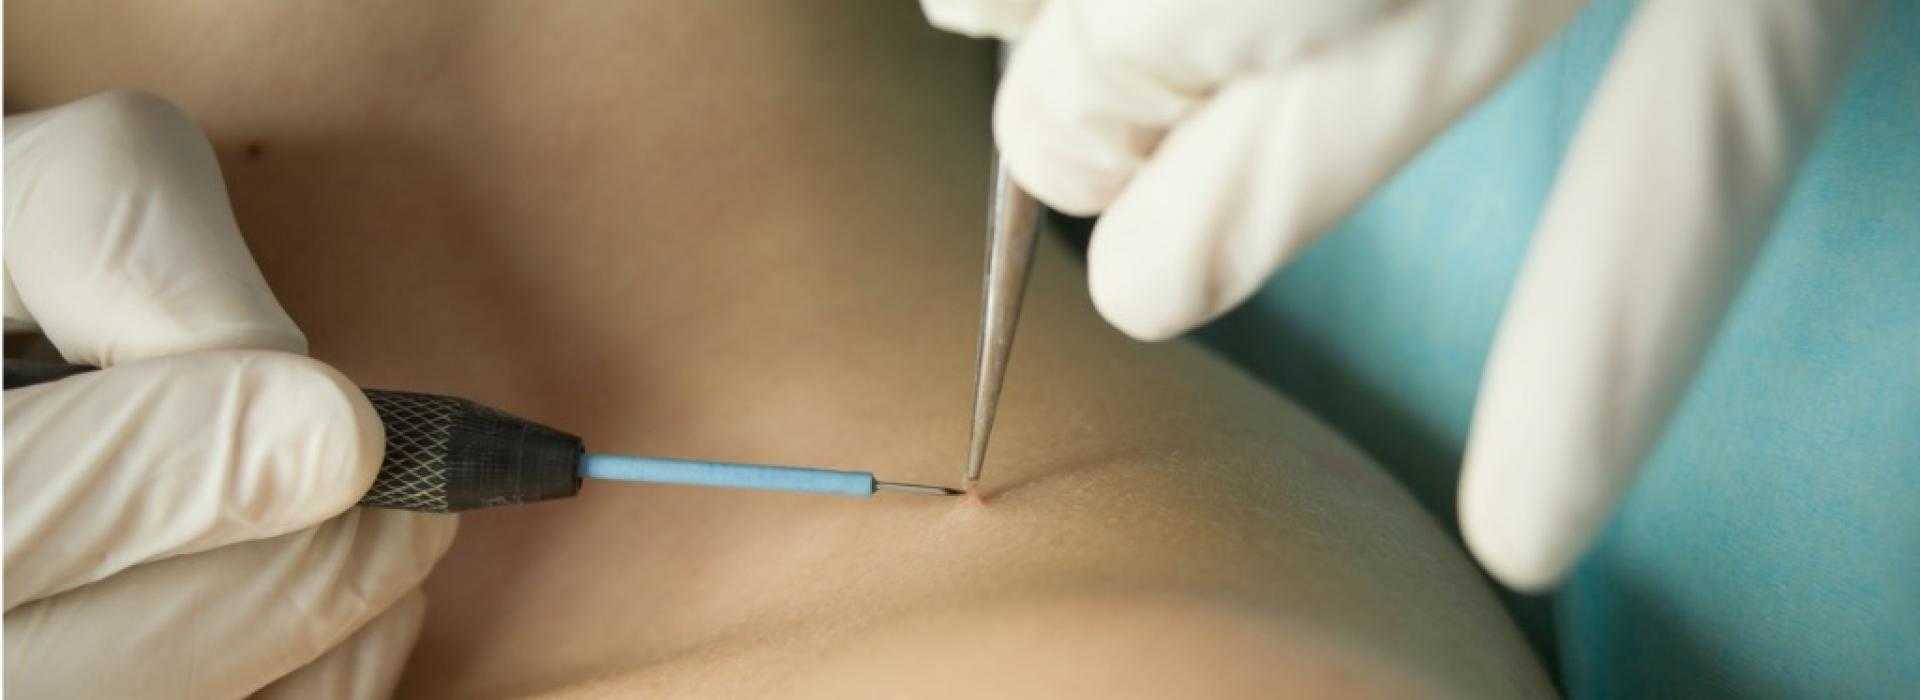

Лечение кондилом требует профессионального медицинского вмешательства. Врач может рекомендовать различные методы лечения, включая применение лекарственных препаратов, криотерапию (замораживание бородавок) или хирургическое удаление.